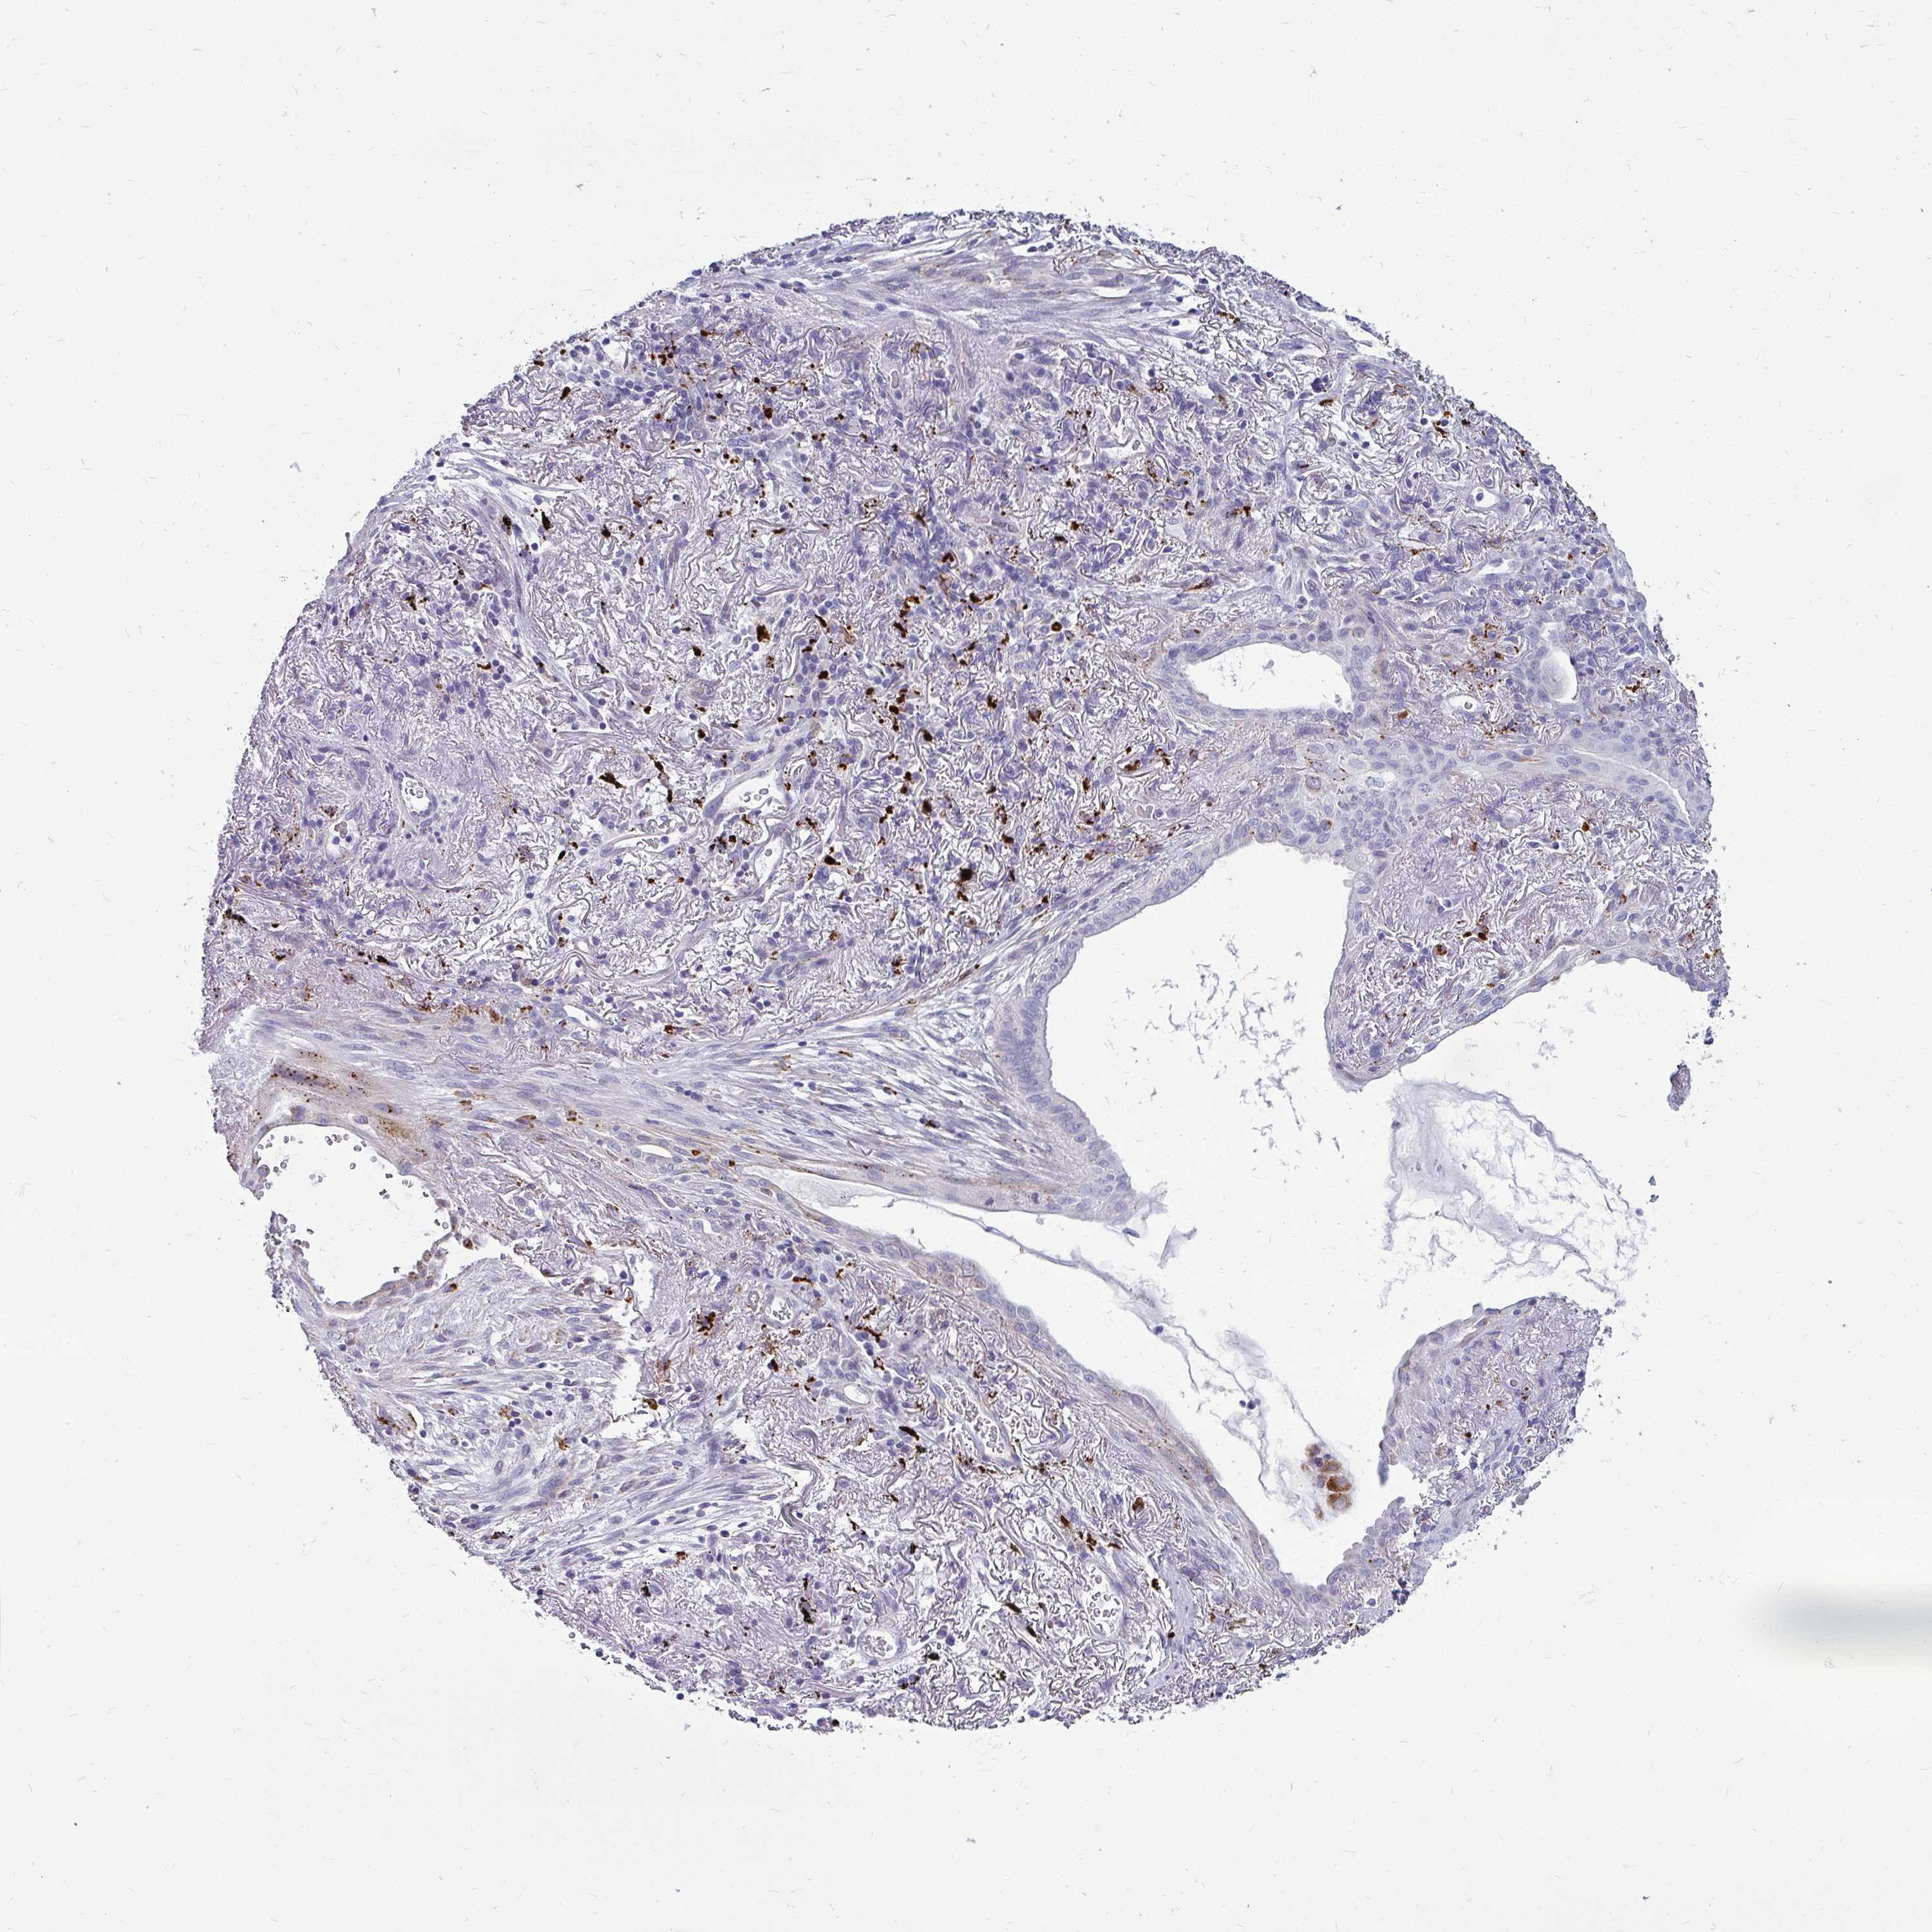

LUNG ADENOCARCINOMA (VALIDATION) - Interactive survival scatter ploti

The Survival Scatter plot shows the clinical status (i.e. dead or alive) for all individuals in the patient cohort, based on the same data that underlies the corresponding Kaplan-Meier plots. Patients that are alive at last time for follow-up are shown in blue and patients who have died during the study are shown in red.

The x-axis shows the expression levels (FPKM) of the investigated gene in the tumor tissue at the time of diagnosis. The y-axis shows the follow-up time after diagnosis (years). Both axes are complimented with kernel density curves demonstrating the data density over the axes. The top density plot shows the expression levels (FPKM) distribution among dead (red) and alive patients (blue). The right density plot shows the data density of the survived years of dead patients with high and low expression levels respectively, stratified using the cutoff indicated by the vertical dashed line through the Survival Scatter plot. This cutoff is automatically defined based on the FPKM cutoff that minimizes the p-score. The cutoff can be changed by dragging the vertical line or by entering a cutoff value in the square labeled "Current cut-off".

Under the Survival Scatter plot the p-score landscape (black curve; left axis) is shown together with dead median separation (red curve; right axis). Dead median separation is the difference in median mRNA expression between patients who have died with high and low expression, respectively. It is calculated as follows: median FPKM expression of dead patients with high expression - median FPKM expression of dead patients with low expression. This is intended to aid the user in visually exploring custom cutoffs and the associated p-scores and dead median separation.

Individual patient data is displayed and can be filtered by clicking on one or more of the category buttons on the top of the page. Categories describing expression level and patient information include: high, low, alive, dead, female, male and tumor stages. The scale of the x-axis can be toggled between linear and log-scale by clicking on the "x log" button. Mouse-over function shows TCGA ID, patient information and mRNA expression (FPKM) for each patient.

& Survival analysisi

Kaplan-Meier plots summarize results from analysis of correlation between mRNA expression level and patient survival. Patients were divided based on level of expression into one of the two groups "low" (under cut off) or "high" (over cut off). X-axis shows time for survival (years) and y-axis shows the probability of survival, where 1.0 corresponds to 100 percent.

CTSZ is not prognostic in Lung Adenocarcinoma (validation)

Best expression cut offi

: 272.58

P scorei

N/A

Average pTPM 215.1

Number of samples 105